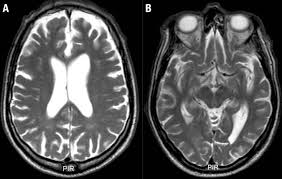

There's still some debate about how common cte is and how it should be diagnosed. A condition seen especially in boxers, caused by repeated cerebral concussions and characterized by weakness in the lower limbs, unsteadiness of gait, slowness of muscular movements, hand tremors, hesitancy of speech, and cognitive impairment. Dementia pugilistica (dp) is a form of chronic traumatic encephalopathy (cte). Frequent concussions can lead to permanent brain damage, resulting in progressively worsening mental faculties. Dementia pugilistica is actually a variant of chronic traumatic encephalopathy (cte), which is itself a serious type of brain damage resulting from repeated concussions and is found in many professional athletes and military personnel who have been subjected to multiple impacts to the head. Cte was previously known as punch drunk syndrome and dementia pugilistica. Originally, the dp article made it seem like the disorders are the same thing. Dementia pugilistica has evolved remarkably over time. The chronic traumatic encephalopathy (cte) article claims that dementia pugilistica (dp) is a variant of cte, so i changed article accordingly. It is predominant among athletes and sportspeople who suffer concussion, e.g, wrestlers, boxers, etc, and present essentially with characteristics of dementia. Dementia pugilistica shares a number of common symptoms with alzheimer's disease, though the two are independently diagnosed. Visible changes results in the brain owing to this damages. Dementia pugilistica is a disorder that develops over several years due to multiple episodes of head trauma.